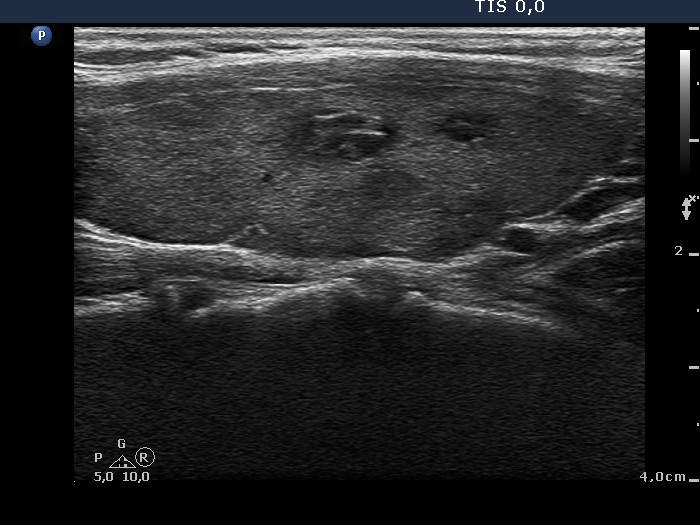

Benign Hashimoto's thyroiditis (cytological diagnosis) - case 1251

First, we demonstrate two cases of Hashimoto's thyroiditis with pronounced fibrotic changes. Both present pale and bright hyperechogenic granules and lines corresponding to normal and excessive connective tissue. Neither of the discrete areas are nodules in a pathological sense.